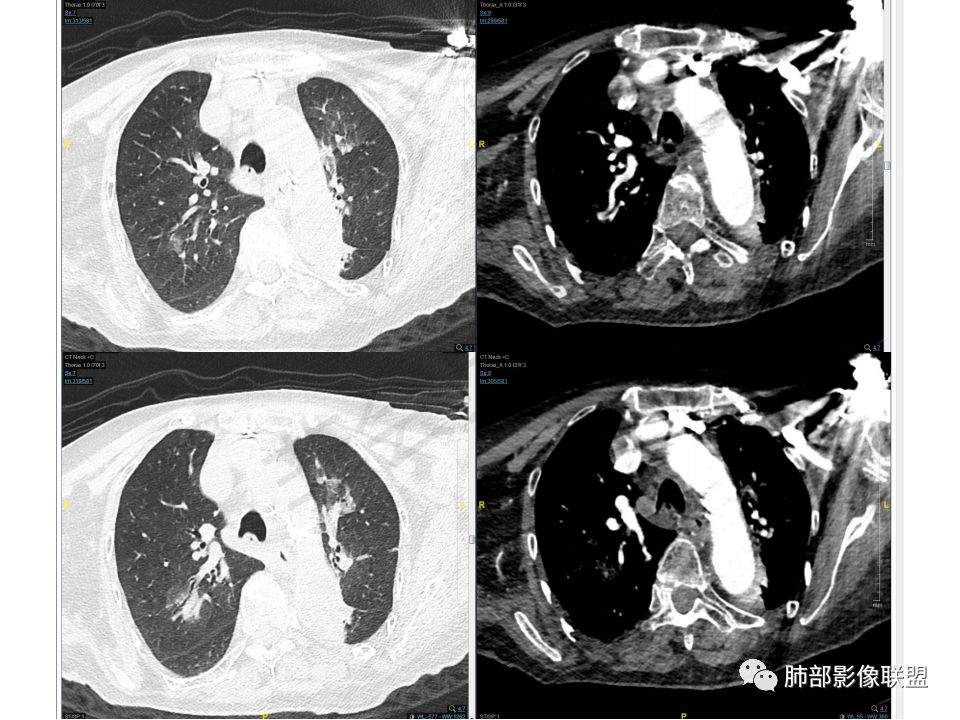

气管腔内占位,强化异常明显,窄基底与粘膜相连,还是带蒂?

两肺结节胸膜下,边缘光滑,强化与气管内病灶一致

左下叶考虑支气管腔内粘液栓堵塞所致

从强化的一致性、形态的一致性,倾向于气管、肺内病灶一元论

强化这么丰富的肿瘤真不多见,形态也一致

1、都是转移瘤,查原发灶。2、气管内恶性肿瘤肺内多发转移